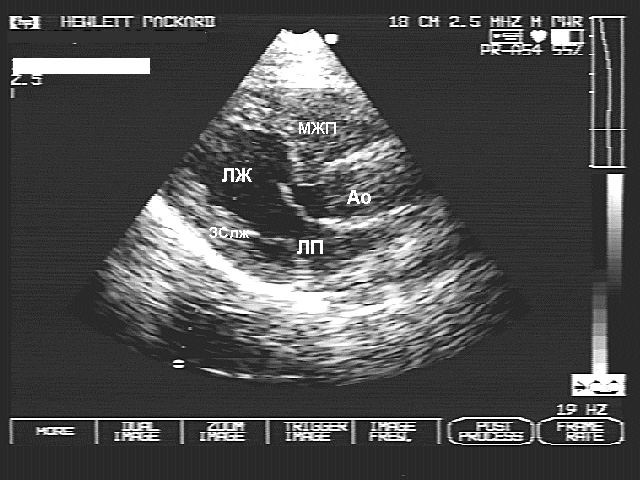

- Эхокардиография — основной метод диагностики. Позволяет оценить выраженность и локализацию гипертрофии, степень обструкции, нарушения диастолической функции и т. д.